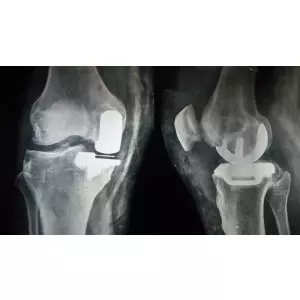

Rahim Sindhi

"movement in just 6 weeks of surgery"